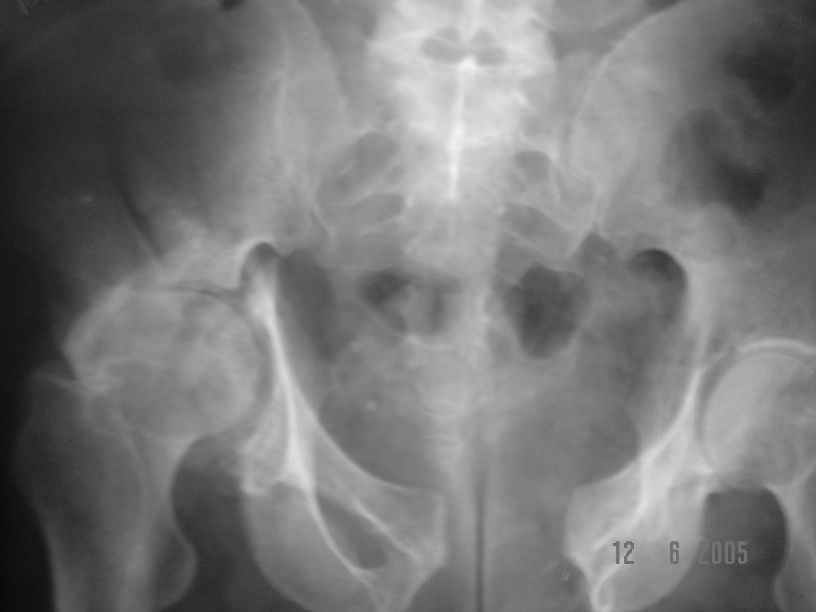

He gives history of being on skin traction for 3,5months. After that he was advised partial weight bearing to be graduated to full weight bearing. Now the patient has difficulty in weight bearing as it is painful. He can walk a few steps only with the help of a walker. Hip movements are restricted and painful. Fl-90* ER-10* IR-0, shortening-4cm. He also had # of humerus and radius/ulna, which were plated and have united. The serial x-rays of the pelvis/Hip during these 5 months show that the hip joint has been in the same position. I have the CT pictures also but not digitalized as yet.

He is 47 years old, Class-1 officer.What are the options? Expert comments please.1. # Pelvis stabilization - Is it possible at 6 mths? And subsequently THR.

2. THR in this position- Cup positioning in a deformed pelvis?

It is a displaced and ununited fracture of the acetabulum, probably type C (AO). The pelvis is not fractured from what one can see of the sacro iliac joint.

Sorry missed the wide open pubic diastasis.